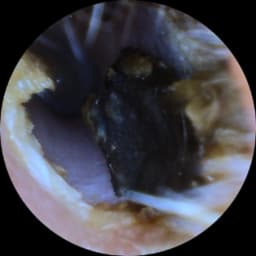

A small camera will assess your membrane health and ear canal. This is a quick painless procedure pictures can be forwarded to your Gp if necessary. Please note we understand if you need to cancel, but a no show you will be charged £25 .Please let us know within 24hrs of your allocated time . PLEASE NOTE THIS IS FREE AND IGNORE IF THE SYSTEM ASKS YOU TO PAY A DEPOSIT!!!I We are trying g to fix this error .